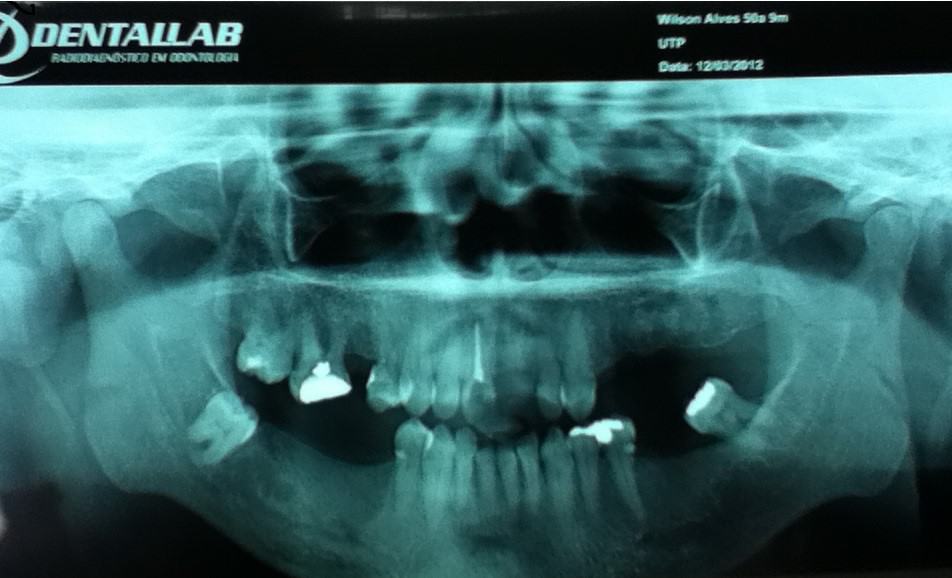

No caso relatado neste trabalho, o atendimento foi realizado no paciente que procurou a clínica da Universidade Tuiuti do Paraná. Por meio de exame intraoral, observou-se a presença de fístula na mucosa vestibular do dente 11, o que ficou comprovado por meio do rastreamento de fístula com cone de guta-percha e posterior exame radiográfico. Este revelou a presença de tratamento endodôntico insatisfatório e lesão periapical do paciente, que procurou a clínica de Odontologia da Universidade Tuiuti do Paraná, pois não ouve sucesso no tratamento endodôntico convencional feito anteriormente feito na própria clínica.

Ao exame radiográfico, observou-se extensa área radiolúcidas, constatando uma fístula, lesão periapical envolvendo região periapical do referido dente.

- Figura 1 – Radiografia panorâmica.